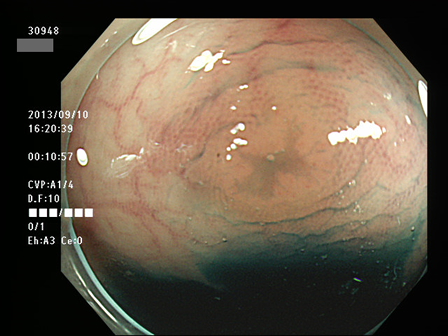

上記100名より抽出した平坦・陥凹型腺腫(=癌化の危険が高いが見落としやすい病変)の内視鏡写真

30943 30946 30947 30948 30949 30950 30952 30956 30958 30960 30961 30962